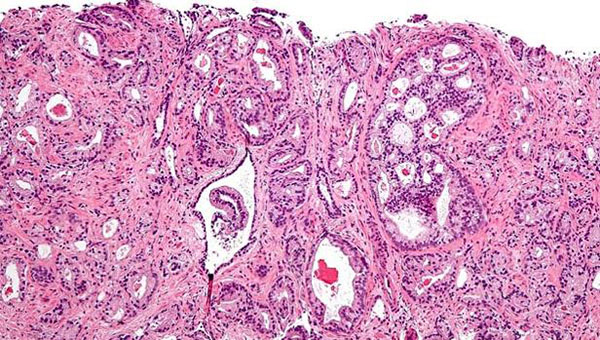

Histología de células tumorales - ARCHIVO

Los tumores de próstata tienden a ser lo que los científicos llaman 'indolentes', es decir, lentos y autónomos, lo que hace que muchos hombres mueren con el cáncer de próstata, no a causa del tumor. Pero para el porcentaje de pacientes cuyos tumores de próstata sufren metástasis, la enfermedad resulta fatal.

A pesar de que se ha sugerido que una dieta occidental puede promover la progresión del cáncer de próstata, hay ausencia de evidencia directa que respalde una asociación entre lípidos dietéticos y el cáncer de próstata, explica el primer autor Ming Chen.

Los estudios epidemiológicos relacionan las grasas (y la obesidad) con muchos tipos de cáncer, y las tasas de muertes por cáncer de cáncer metastásico, incluido el cáncer de próstata, son mucho más altas en EE.UU. que en las naciones donde las dietas bajas en grasas son más comunes. Si bien el cáncer de próstata afecta aproximadamente al diez por ciento de los hombres en las naciones asiáticas, ese índice sube a cerca del 40% cuando residen en los EE. UU. Eso sugiere que existe un responsable ambiental que pueda colaborar con los factores genéticos para convertir esta enfermedad en agresiva y fatal.